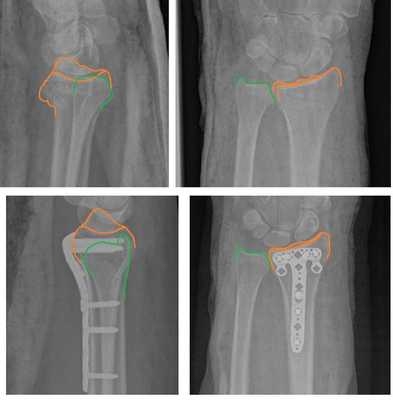

Рис. 4. Компьютерная томограмма с нестабильным переломом лучевой кости.

Рис. 5. Состояние после операции: полное восстановление структуры лучевой кости.

На представленной рентгенограмме не тренированный глаз может вообще не увидеть перелома, хотя врач травматолог и квалифицированный рентгенолог заметят насколько «просела» суставная поверхность лучевой кости, и отметят, что она развёрнута в тыльную сторону на 10 градусов (в норме она должна смотреть в ладонную сторону). Если присмотреться повнимательнее становятся видны линии перелома.

Намного более отчётливо степень нестабильности этих костных фрагментов видна под ЭОП-ом при выполнении функциональных проб. При тыльном сгибании определяется значительное количество мелких фрагментов тыльной кортикальной пластинки и внутрисуставной, оскольчатый характер перелома.

В такой ситуации лечение консервативным способом, гипсовой повязкой, не может дать надёжного результата. При оскольчатом характере перелома с дефектом тыльной кортикальной пластинки у дистального метаэпифиза просто нет надёжной опоры, и в итоге происходит усугубление смещения, суставная поверхность ещё больше наклоняется в тыльную сторону.

По этой причине в нашей клинике мы предпочитаем лечить такие типы переломов оперативно. Для фиксации данного типа повреждений предпочтительно использовать пластины с угловой стабильностью с дистальным расположением винтов, которые можно ввести субхондрально, ближе к суставной поверхности. В своей практике мы используем пластины фирмы Synthes - 2.4mm Variable Angle LCP® Volar Rim Distal Radius System.

Такой тип фиксации позволяет добиться стабилизации перелома, отказаться от гипсовой иммобилизации и начать раннюю разработку движений в лучезапястном суставе, что в конечном счёте приводит к отличным функциональным результатам. Оперативное вмешательство целесообразно проводить непосредственно в день травмы, до нарастания отёка, оптимально - в первые 6 часов после травмы.